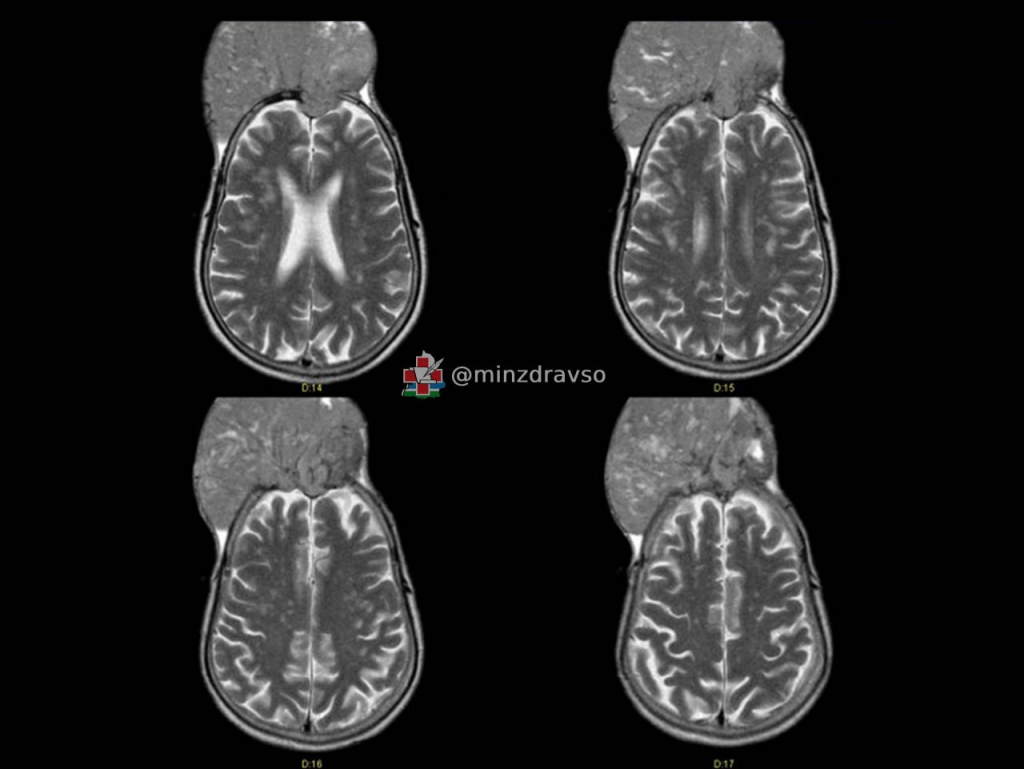

Специалисты Свердловского областного онкологического диспансера спасли краснотурьинца с менингиомой крыла клиновидной кости, которая буквально «съела» череп. Одна из самых распространённых опухолей мозга является доброкачественной, но может вызывать нарушения слуха, зрения, речи, чувствительности, двигательной активности, а без своевременной терапии способна создать угрозу жизни пациента. Нейрохирурги успешно провели мужчине семичасовую операцию, удалив новообразование.

«Житель Краснотурьинска поступил в отделение нейроонкологии, когда опухоль уже проросла кости черепа и распространилась наружу примерно на 10 сантиметров. При этом она не вызвала никаких симптомов. На вопрос, почему пациент так долго не обращался к врачам, хотя "вторая голова" росла буквально на глазах, мужчина ответить затруднился. В итоге новообразование достигло размеров примерно 15 на 15 сантиметров», — рассказал нейрохирург Свердловского областного онкодиспансера Павел Гвоздев.

Напомним, что 22 июля отмечается Всемирный день мозга. На долю менингиомы приходится 30% всех случаев новообразований мозга, также встречаются различные варианты аденом гипофиза, опухоли оболочек нервов и другие новообразования. Самые опасные — злокачественные глиомы, молниеносно растущие из клеток мозга: от начала заболевания до патологического состояния может пройти всего пара месяцев. Характеризуются глиомы яркими неврологическими нарушениями, поэтому медики настоятельно рекомендуют при появлении такого рода симптомов у себя или своих близких незамедлительно обратиться к неврологу. Самый эффективный метод диагностики заболеваний мозга — магнитно-резонансная томография. Лечение, как правило, комплексное, оно может включать хирургию, лучевую и лекарственную терапию или один из этих методов. Ежегодно нейрохирурги Свердловского областного онкологического диспансера выполняют более 700 операций на головном мозге.